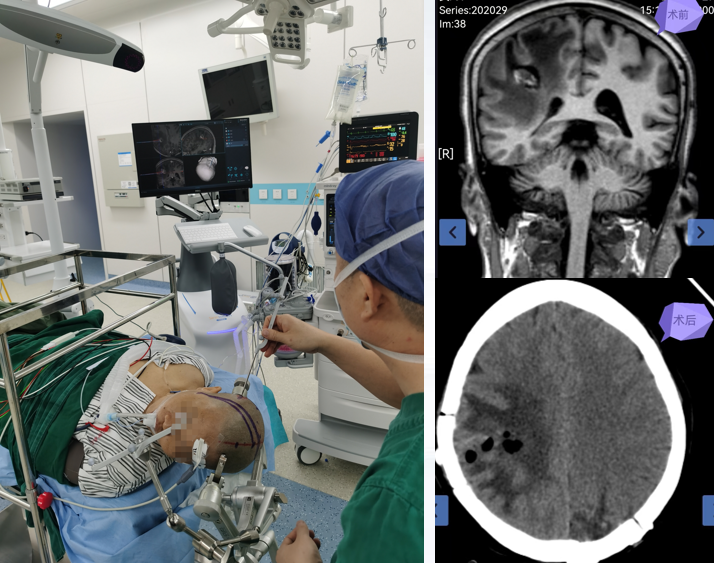

图片 2.png

应用微型机器人进行弥漫中线胶质瘤精准穿刺活检手术

以该院常规开展的原发性中枢神经系统淋巴瘤和丘脑胶质瘤活检手术为例,术中使用神经导航&微型机器人系统,可将手术误差控制在0.1毫米以内,比传统的“盲穿”方式在精度上有了几何倍的提高。通过采用这种导航微型机器人技术,实现了对脑深部病变治疗的精准化、微创化和智能化,不仅显著降低了手术风险,还减少了术后并发症的发生,为病人带来了更好的治疗效果和康复体验。